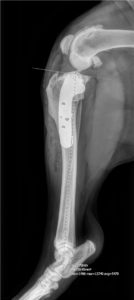

Les traumatismes des membres sont fréquents : chat qui chute d’un balcon, chien heurté par une voiture, accident de chasse, etc… Beaucoup de fractures nécessitent un traitement chirurgical (ostéosynthèse par broche ou plaque par exemple), rare sont les fractures sur lesquelles un plâtre ou une résine peuvent être posées.